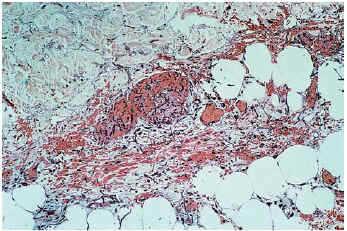

Se realizó biopsia de una de las lesiones y toma de muestra para cultivo microbiológico. El estudio histológico, confirmado con PAS, demostró la presencia de hifas tabicadas y ramificadas localizadas por toda la dermis e hipodermis con invasión masiva de los vasos (figs. 2 y 3). El cultivo microbiológico fue positivo para Aspergillus niger.

Fig. 2.--Presencia de múltiples hifas tabicadas y ramificadas en dermis profunda e hipodermis con invasión vascular (hematoxilinaeosina ×10).

En el estudio histológico de las lesiones cutáneas con la tinción de ácido periódico de Schif (PAS) o con metamina-plata se observan hifas tabicadas, ramificadas en ángulo agudo y con tendencia a la invasión y trombosis de los vasos, que es muy orientativa de infección por Aspergillus sp.; no obstante, hay que hacer el diagnóstico diferencial con otras micosis de la especie Fusarium sp. y Pseudallescheria boydii, por lo que el diagnóstico de confirmación se obtiene con el crecimiento del hongo en medio de Saboraud4, 17.